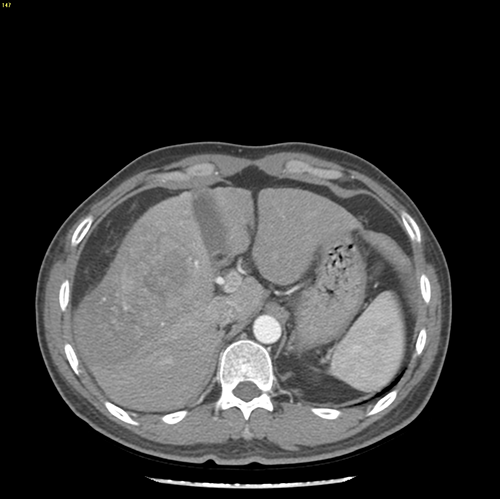

右肝巨大肝癌---右半肝切除